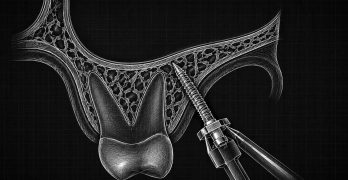

Microimplantes y un arco auxiliar de torsión de cuatro curvaturas para tratar la fenestración radicular labial de incisivos superiores

El artículo de este miércoles es un reporte de caso, llamado Combined use of microimplants and a self-made … [Leer más...] acerca de Microimplantes y un arco auxiliar de torsión de cuatro curvaturas para tratar la fenestración radicular labial de incisivos superiores